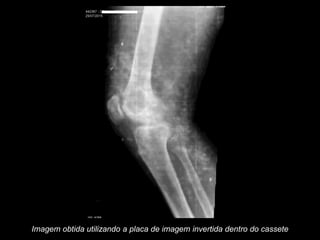

Imagem obtida utilizando a placa de imagem invertida dentro do cassete